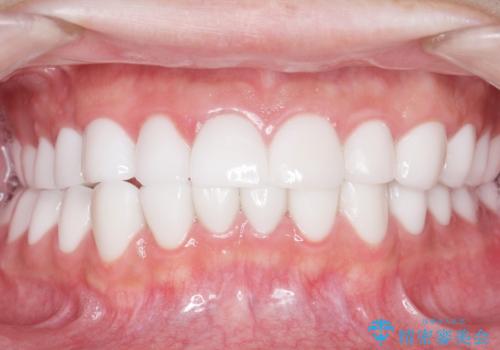

憧れのヴィジュアル系バンドマンのような白い歯になり、喜んで下さいました。

不適なレジン充填によるデコボコがなくなったことで歯磨きしやすくなり、また気にされていた咬み合わせも良くなり、ご満足頂けました。

クラウンの種類:オールセラミッククラウン スタンダード

シェード:NW0